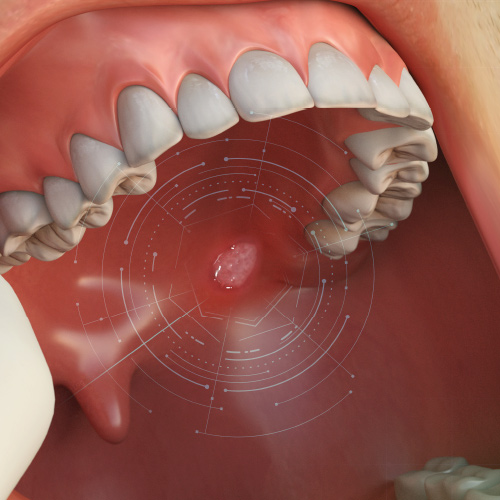

Innovations in Specialty Care Dentistry

This Compendium eBook offers a continuing education (CE) article on the future of oral cancer diagnosis. A second CE article discusses diagnosis and management of oral allergy syndrome (OAS).

Oral Surgery Advances

This Compendium eBook offers a continuing education (CE) article that examines how clinicians can enhance biopsy techniques with the use of a dental laser. Also included in this eBook is a case report article, highlighting two case studies, on the use of a crosslinked collagen membrane in c...